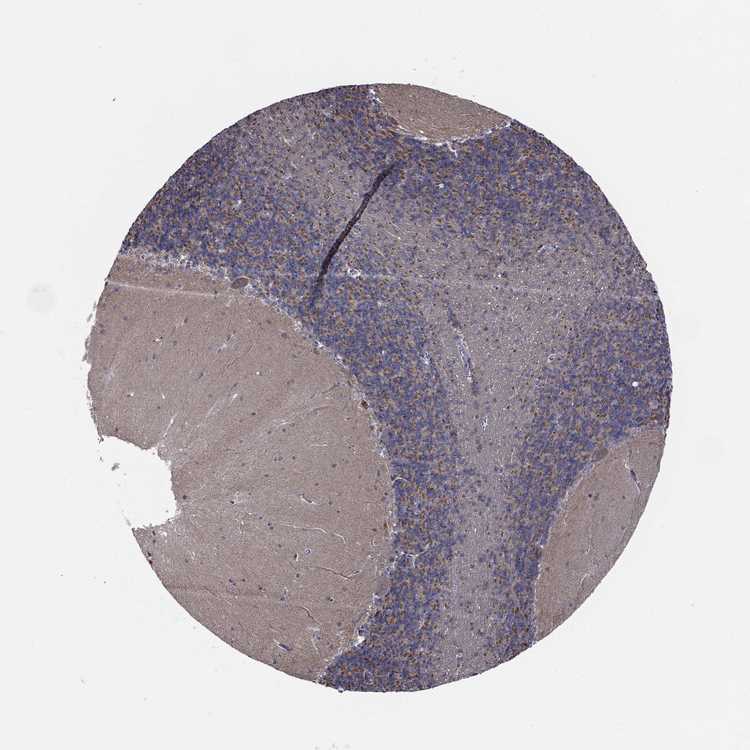

BRAIN CEREBELLUM Show tissue menu

CEREBELLUM - Expression summary

CEREBELLUM - Antibody stainingi

Antibody staining in the annotated cell types in the current human tissue is reported as not detected, low, medium, or high, based on conventional immunohistochemistry profiling in selected tissues. This score is based on the combination of the staining intensity and fraction of stained cells.

Each image is clickable and will lead to virtual microscopy that enables deeper exploration of all samples and also displays staining intensity scores, fraction scores and subcellular localization as well as patient and tissue information for each sample.

Antibody HPA044620Antibody HPA058621

Purkinje cells LowLow

Cells in granular layer LowNot detected

Cells in molecular layer MediumNot detected